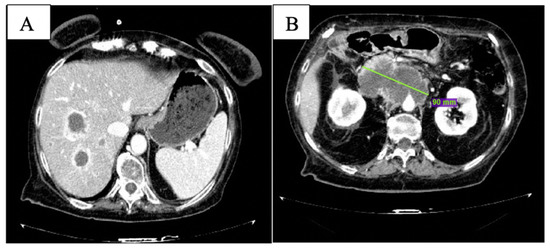

After the 6th month of therapy with olaparib, clinical conditions worsened with uncontrolled abdominal pain and G3 fatigue per CTCAE v. 5.0 [13]. At CT scan, multiple new liver lesions were observed (Figure 4A); the peripancreatic tissue was augmented with celiac trunk encasement (Figure 4B). Peritoneal carcinosis was also evident.

Figure 4.

CT scan after 6 months of olaparib: new liver lesions are documented (A) and peripancreatic tissue is increased (B).